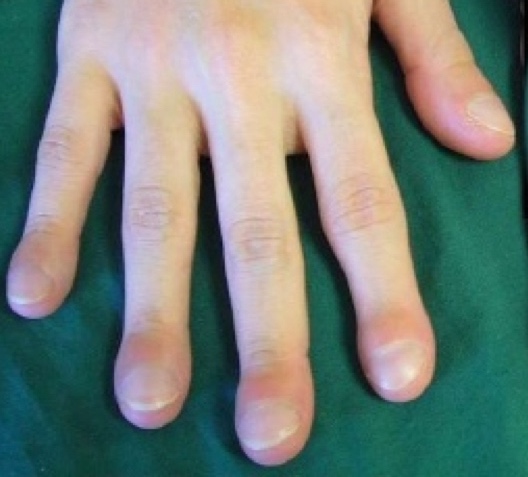

Image of acropachy in fingertips.

As years pass, a sustained left-to-right shunt causes an increase in pulmonary pressure and histological changes of the pulmonary vessel thereby generating pulmonary hypertension. Over time, this increase in flow causes an increase in the thickness of the tunica media (muscular middle layer) and, consequently, an increase in pulmonary resistance which becomes irreversible. This is known as Einsenmenger’s Syndrome, where the shunt remains irreversibly inverted, causing cyanosis (right-to-left shunt). Another secondary complicationof the shunt is the risk of endocarditis. In CHDs that cause cyanosis, there is a compensatory increase in the production of haemoglobin, causing polyglobulia, which, in turn, causes problematic abscesses due to hyperviscosity of the blood. The bony deformations of the fingers (acropachy or “drumstickfingers”) are deformations of the distal phalanges of the fingers and toes caused by hyperproduction of blood in the bones in those locations.